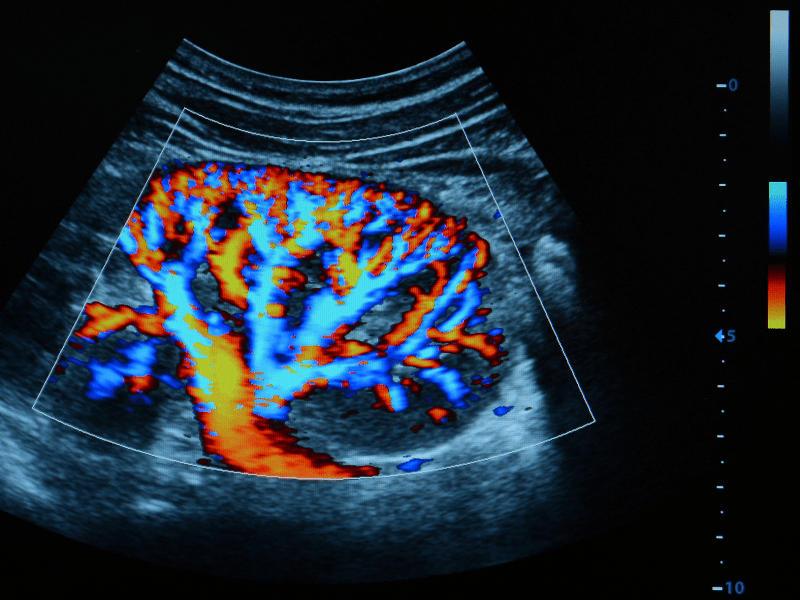

L’ecocolordoppler Napoli è un esame diagnostico non invasivo che utilizza gli ultrasuoni per visualizzare i vasi sanguigni (arterie e vene) e studiare il flusso del sangue al loro interno.

- Sfrutta l’effetto Doppler per misurare la velocità  e la direzione del flusso sanguigno.

- Il colore viene utilizzato per rappresentare la direzione del flusso (rosso per il flusso verso la sonda, blu per il flusso lontano).